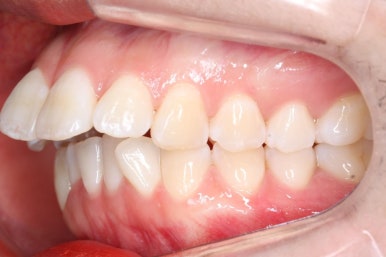

다시 이번 환자분으로 돌아가, 입 안모습을 보시겠습니다.

부산무턱교정 키다리아저씨치과에서 처음 내원하셨을 당시의 입 안의 모습입니다.

아래턱이 작아서 상대적으로 윗니들이 많이 돌출되었고, 뻐드러져 있습니다. 윗니들이 배열되어 있는 형태도 V자에 가깝게 입천장이 좁은 양상입니다.

중앙선도 잘 맞고 교합도 잘 마무리되었습니다.

중앙선, 교합, 뻐드러짐 모두 좋아졌고 이를 뽑고 교정했지만 발치 공간이 남지 않고 잘 마무리 되었습니다.